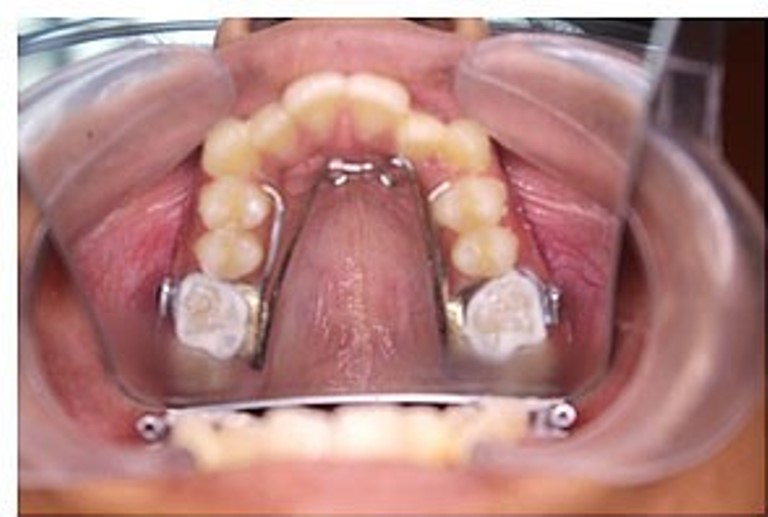

Một loại khí cụ khác có thể được sử dụng trong chỉnh nha sớm là nong hàm (Quad helix), giúp mở rộng vòm miệng và tạo thêm khoảng trống cho răng. Điều này có thể đặc biệt có lợi cho trẻ em có hàm hẹp. Điều trị này rất đơn giản nhưng giúp tránh được việc điều trị xâm lấn như nhổ răng hoặc phẫu thuật hàm sau này.

Khí cụ Quad-helix nong hàm